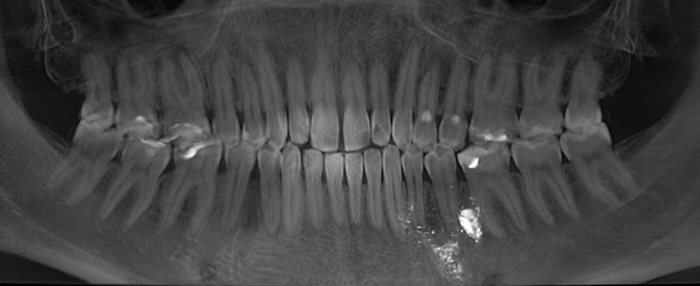

Контрольная ортопантомограмма:

Прицельный снимок:

Я согласен, что эстетика хромает. Давно пора менять временную коронку на постоянную, что улучшит результат. Но, как я говорил, все упирается в финансы.